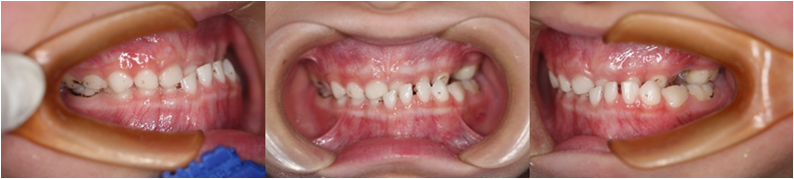

3.异常咀嚼习惯

过软的食物使得咀嚼功能不能充分发挥,影响颌骨发育,造成牙量骨量不调,牙齿拥挤不齐。

偏侧咀嚼习惯,下颌向健侧偏斜,造成健侧后牙对刃或反𬌗,下中线偏向健侧,使健侧形成远中错𬌗,失用侧形成近中错𬌗及深覆盖或锁𬌗。